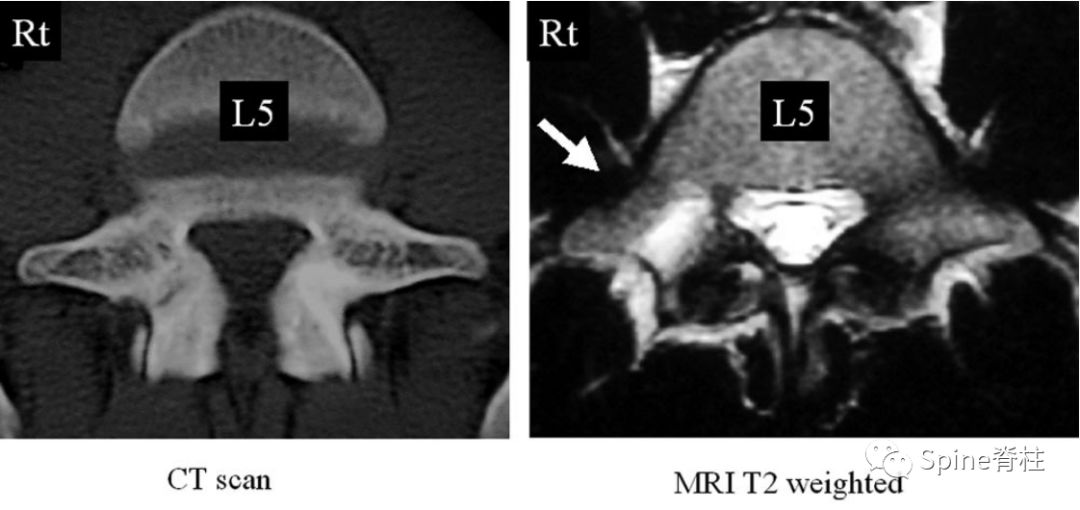

有研究发现磁共振上 椎弓根出现T2高信号改变是青少年和儿童峡部裂的早期诊断征象 。同时, 存在椎弓根高信号改变也是保守治疗后能达到骨性愈合的良好预测指标 (也就是说存在T2椎弓根右高信号改变的峡部裂患者,其峡部裂经保守治疗愈合的可能性大) 。

Sairyo教授研究发现磁共振上 椎弓根出现T2高信号改变是青少年和儿童峡部裂的早期诊断征象 。同时,存在椎弓根高信号改变也是保守治疗后能达到骨性愈合的良好预测指标(也就是说存在T2椎弓根右高信号改变的峡部裂患者,其峡部裂经保守治疗愈合的可能性大)。

右图提示椎弓根高信号改变(箭头)

右图提示双侧椎弓根高信号改变(箭头)

右图:右侧椎弓根高信号改变明显,左侧椎弓根轻微高信号